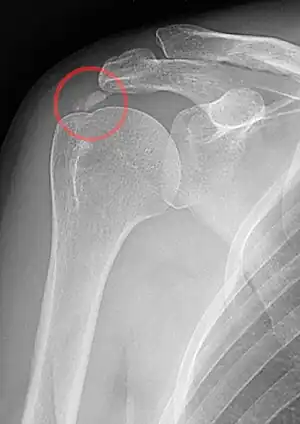

An x-ray showing calcific deposits in the area of the tendons of the rotator cuff muscles